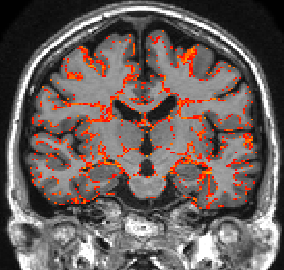

This section investigates the number of Monte Carlo samples and the segmentation performance of the proposed network. Fig. 8(a) suggests that using samples is enough to achieve good segmentation. Further increasing the number of samples has relatively small effects on the DCS. Fig. 8(b) plots the voxel-wise segmentation accuracy computed using only the voxels with an uncertainty less than a threshold. The voxel-wise accuracy is high when the threshold is small. This indicates that the uncertainty estimation reflects the confidence of the network. Fig. 9 shows an uncertainty map generated by the proposed network. The uncertainties near the boundaries of different structures are relatively higher than the other regions.

With this theoretical insight, we are able to estimate the uncertainty of the segmentation map at the voxel level. We extend the segmentation network with a convolutional layer before the last convolutional layer. The extended network is trained with a dropout ratio of 0.5 applied to the newly inserted layer. At test time, we sample the network N times using dropout. The final segmentation is obtained by majority voting. The percentage of samples which disagrees with the voting results is calculated at each voxel as the uncertainty estimates.